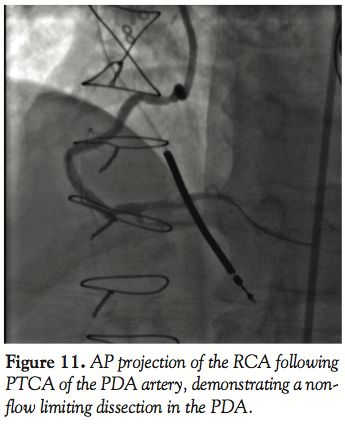

Case 4. In this case, another potential advantage of the GuideLiner is highlighted. A 66-year-old male presented with stable angina and a history of prior CABG and inferior ischemia on noninvasive perfusion imaging. The culprit lesion was identified in the PDA. The proximal and mid RCA were previously stented, the ostium of the RCA was anterior, and the vessel was very tortuous proximally (Figures 10 and 11). A 7 Fr AL 0.75 guiding catheter engaged the RCA ostium coaxially. After a BMW wire was used to cross the lesion,

predilatation of the lesion was performed with a 2.75 mm balloon and then the GuideLiner catheter was advanced past the previously placed stents (Figure 12). This permitted placement of a 2.75 mm x 23 mm Promus (Boston Scientific) DES with relative ease (Figure 13). The GuideLiner allows delivery of stents distally past previously placed stents, which is an advantage in cases like this when there is a new de novo lesion beyond previously placed stents or even in difficult cases in stenting a distal dissection after placement of freshly placed stents. This challenges the well-established dictum of stenting from distally in the vessel to proximally in the vessel because the atraumatic soft tip of the GuideLiner catheter can easily be placed past freshly placed stents for extra support to deliver a stent distally in the vessel.